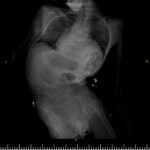

SAMSUN (AA) – Samsun'da, skolyoz (omurga eğriliği) nedeniyle nefes almakta zorluk çeken ve kaburgaları kırılmaya başlayan serebral palsi hastası Enes Serçe, ameliyatla sağlığına kavuştu.

Enes Serçe'nin omurgasındaki eğrilik hastanede 5,5 saat süren ameliyatla giderildi.

Hastanın, omurga eğriliğinde artma, solunum kapasitesinde azalma, iç organ baskılarının artması ve kaburgalarının kırılmaya başlaması nedeniyle ameliyat edildiğini anlatan Bozduman, "Hastamızı yaklaşık 5,5 saatlik ameliyatla başarıyla tedavi ettik. Yedi gündür hastamızı takip ediyorduk, artık taburcu edilebilir duruma geldi." dedi.